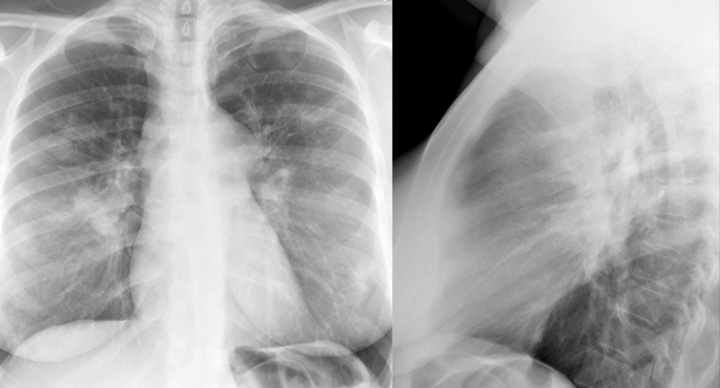

Gallery Sarcoid Sarcoid Case 18 PA & Lat

Case 18 PA & Lat